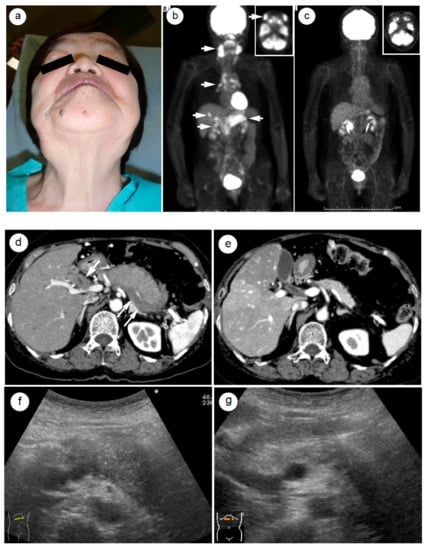

- Matsubayashi, H.; Furukawa, H.; Maeda, A.; Matsunaga, K.; Kanemoto, H.; Uesaka, K.; Fukutomi, A.; Ono, H. Usefulness of Positron Emission Tomography in the Evaluation of Distribution and Activity of Systemic Lesions Associated with Autoimmune Pancreatitis. Pancreatology 2009, 9, 694–699. [Google Scholar] [CrossRef]

- Shigekawa, M.; Yamao, K.; Sawaki, A.; Hara, K.; Takagi, T.; Bhatia, V.; Nishio, M.; Tamaki, T.; El-Amin, H.; Sayed, Z.-A.; et al. Is (18)F-fluorodeoxyglucose positron emission tomography meaningful for estimating the efficacy of corticosteroid therapy in patients with autoimmune pancreatitis? J. Hepatobiliary Pancreat. Sci. 2010, 17, 269–274. [Google Scholar] [CrossRef]

- Matsubayashi, H.; Yoneyama, M.; Nanri, K.; Sugimoto, S.; Shinjo, K.; Kakushima, N.; Tanaka, M.; Ito, S.; Takao, M.; Ono, H. Determination of steroid response by abdominal ultrasound in cases with autoimmune pancreatitis. Dig. Liver Dis. 2013, 45, 1034–1040. [Google Scholar] [CrossRef]

- Matsubayashi, H.; Uesaka, K.; Kanemoto, H.; Aramaki, T.; Nakaya, Y.; Kakushima, N.; Ono, H. Reduction of splenic volume by steroid therapy in cases with autoimmune pancreatitis. J. Gastroenterol. 2013, 48, 942–950. [Google Scholar] [CrossRef]